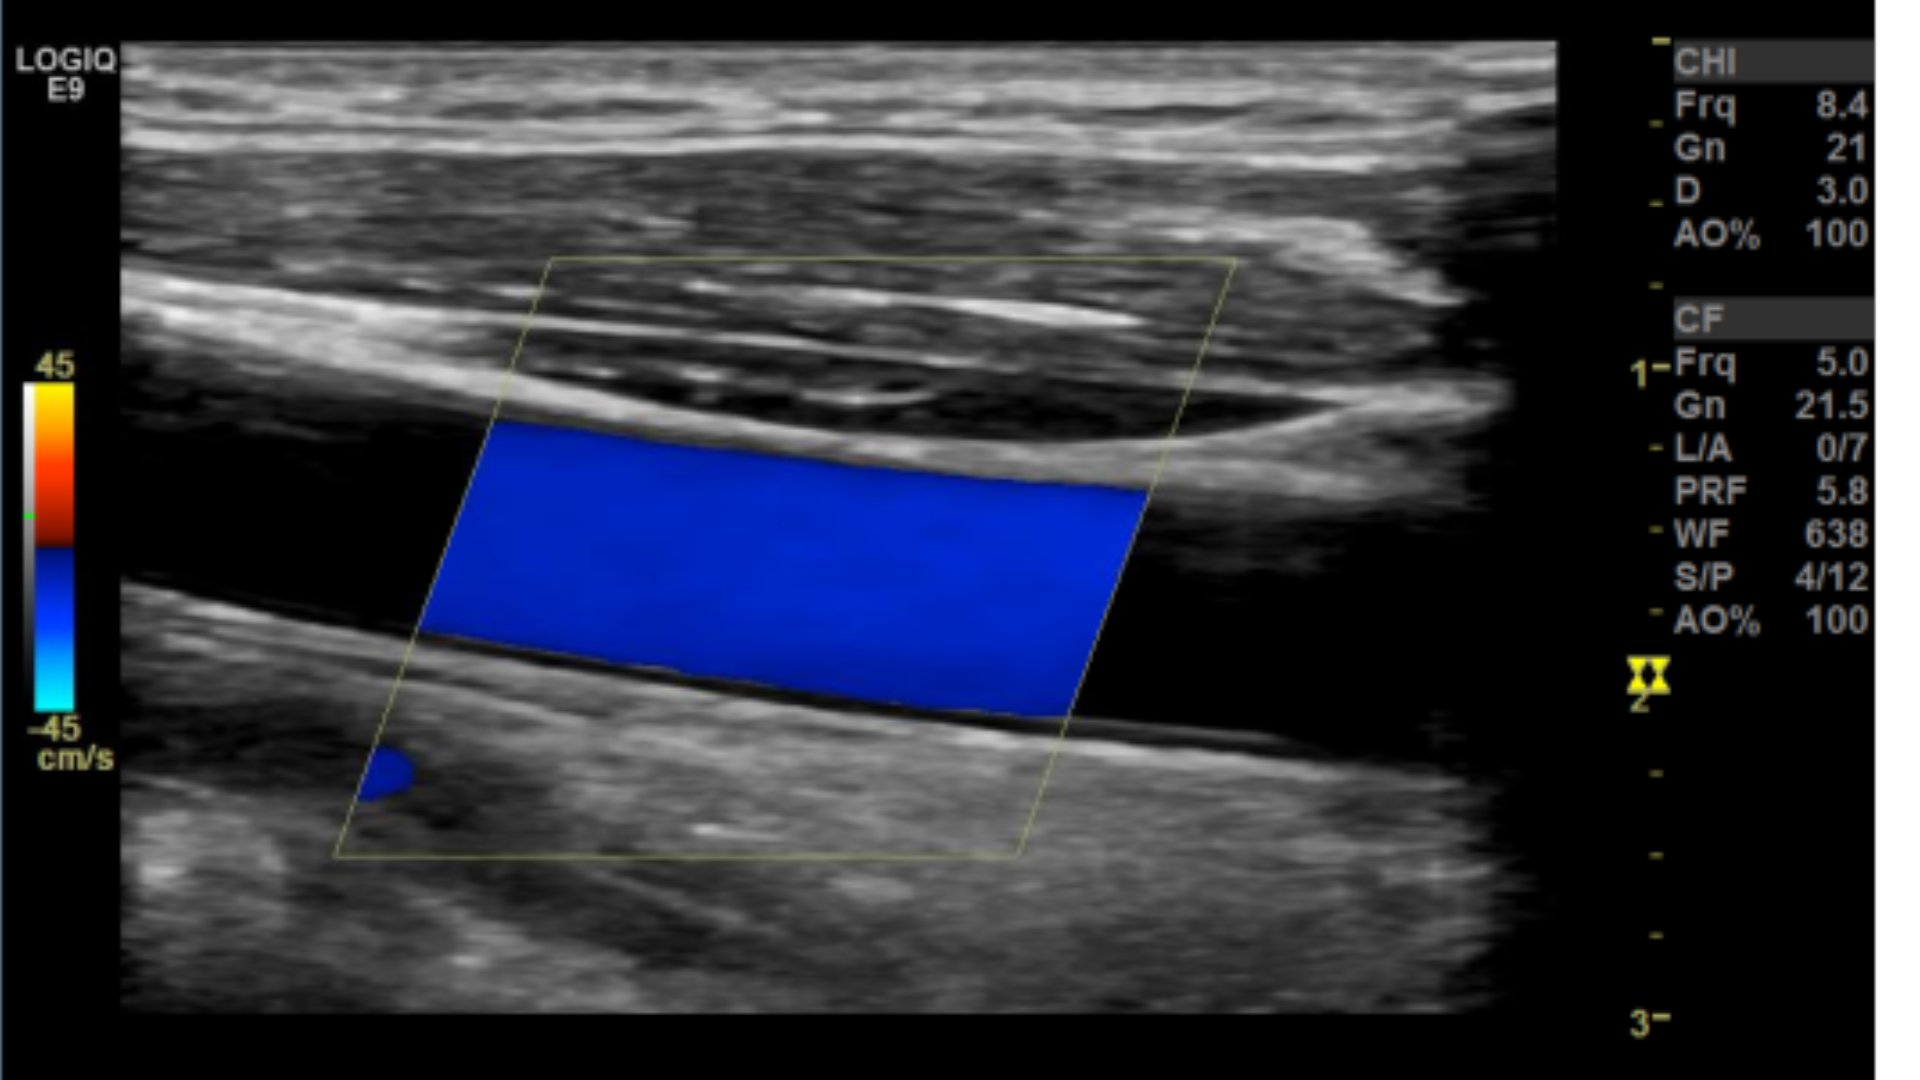

Many people have trouble on how to set the color box. A quick way to get it right is to make sure the steered ultrasound beam and vessel meet an acute angle 60° or less.

Correct Color box angle

Sub-optimal angle

Incorrect angle